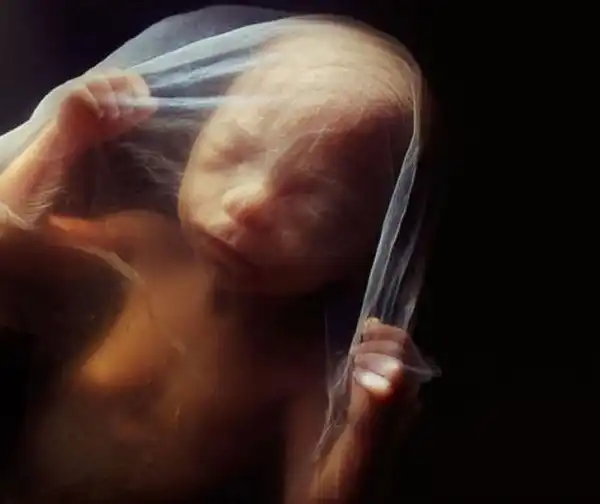

10 недель. Веки уже полуоткрыты. В течение нескольких дней они сформируются полностью.

10 недель. Малыш уже использует руки для изучения окрестностей